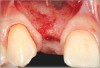

Fig 8. Submerged implant protocol, occlusal view. A horizontal releasing incision was sutured to attain primary closure. Note that there are no sutures through the thin retained papillary segments.

Figure 8